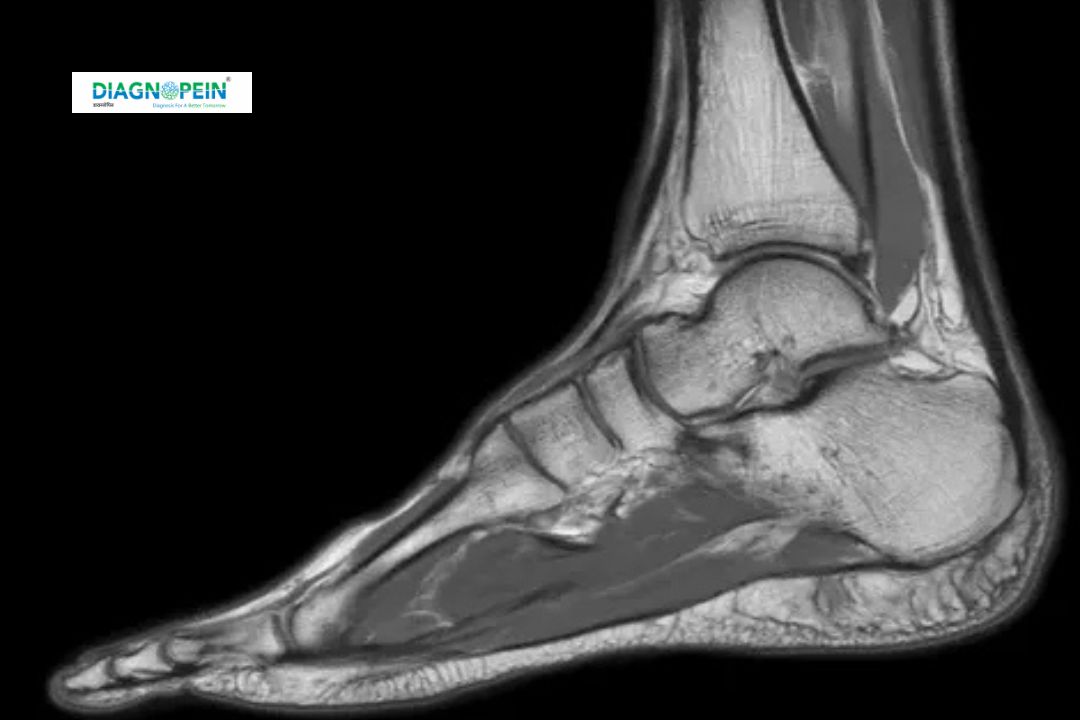

MRI Ankle is a specialized imaging test that creates highly detailed pictures of the ankle's bones, ligaments, tendons, cartilage, and soft tissues using magnetic resonance technology. Unlike X-rays, MRI does not use radiation and provides 3D, cross-sectional images allowing for precise detection of injuries and abnormalities. This scan is essential to diagnose ankle pain causes, sports injuries, arthritis, infections, tumors, and other soft tissue conditions that are not visible on standard imaging.